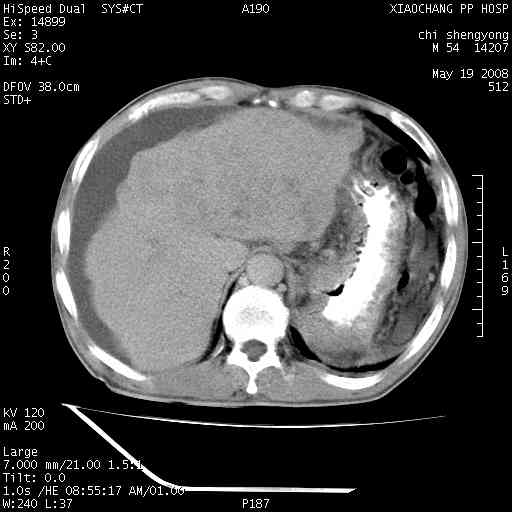

以下是引用zjzjr在2008-5-21 10:52:00的发言:[br]肝左叶巨块型肝癌伴门静脉左支瘤栓形成.肝硬化、腹水,胃底静脉曲张,脾术后改变。

以下是引用随光逐影在2008-5-21 16:20:00的发言:[br]1)肝左叶肝癌伴门静脉左支瘤栓形成,腹膜后淋巴结转移。2)肝硬化、腹水、胃底静脉曲张。3)胆囊炎。4)脾脏缺如,为切除术后所致。